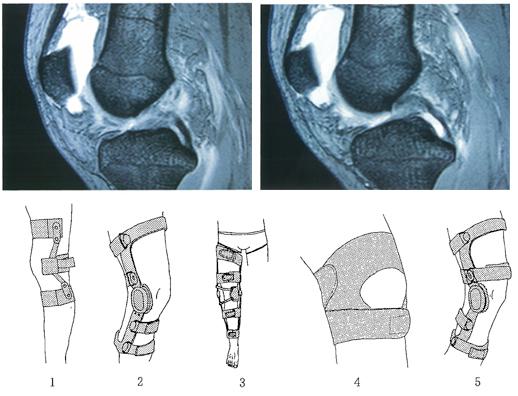

18歳の男性。サッカーの試合中に方向転換しようとして膝関節をひねり、疼痛のため歩行不能となった。翌日に撮像したMRIを示す。2週後に歩行可能となったが、膝関節に不安定感がある。適応となる装具はどれか。

7e8wUVAbF6dnJTnYT6XlS

1

2

3

4

5